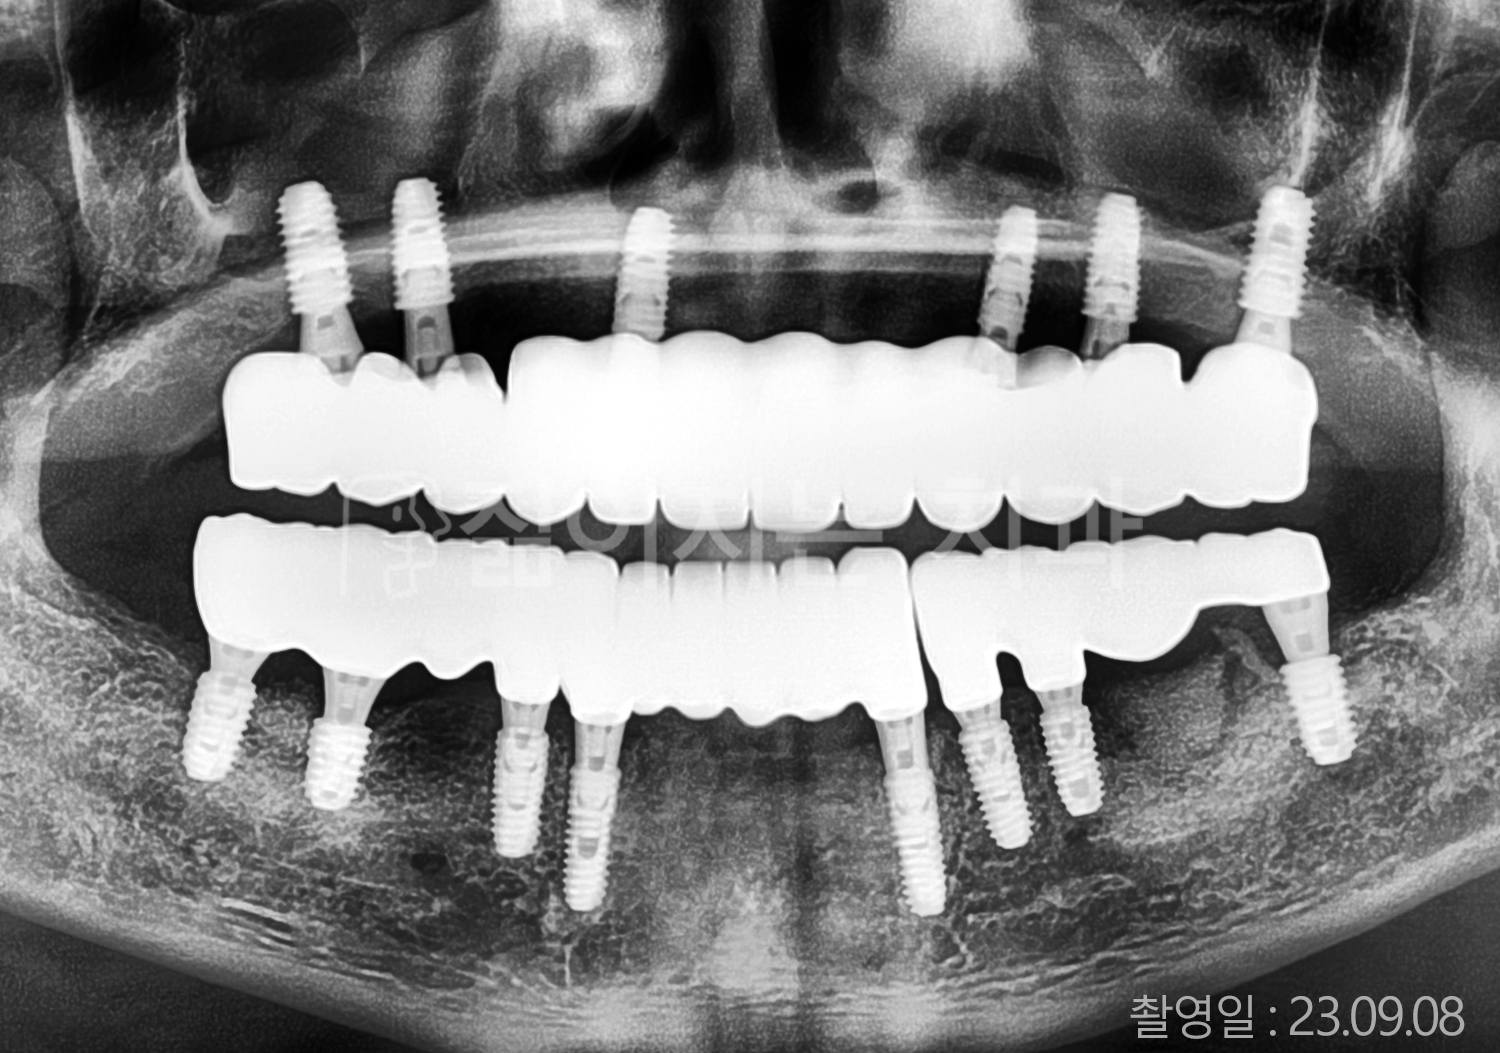

• 50대 전체치아 10개 이상 임플란트